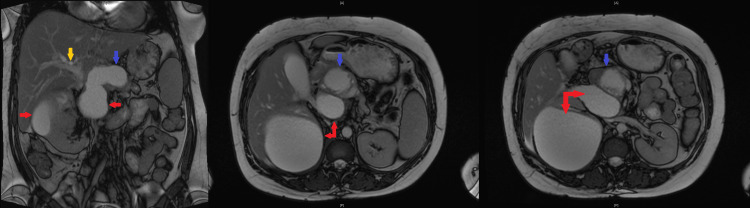

CT abdomen suggested recurrence of the pseudocyst in the pancreatic head, causing compression of the CBD and PD leading to dilatation of upstream PD, CBD, and intrahepatic biliary ducts. There was a further large cyst measuring 6.6 x 3.7 cm posterosuperior to the pancreas along with a larger right renal cyst. MRI confirmed evidence of chronic pancreatitis and two pancreatic pseudocysts. One of the cysts in the head of the pancreas measuring 4.8 x 4.6 cm was causing local pressure effect on the CBD, and there was intra and extrahepatic biliary dilatation with the CBD measuring up to 15 mm (previously 13 mm) (Figure 3). The cyst was also causing compression of the pancreatic duct, which was dilated to approximately 7 mm. The other large peripancreatic cyst measuring about 7 x 4 cm located posterosuperior to the body of pancreas had ruptured causing collection sized 12.9 x 11.2 x 13.0 cm, compressing on the right renal capsule (Figure 4).

Ultrasonography-guided percutaneous drainage of the cyst was performed. The fluid obtained from the drainage was turbid and bloody with no growth of microorganisms on culture and negative for malignant cells on cytology. Following the drainage, an endoscopic retrograde cholangiopancreatography (ERCP) was performed that showed a distal CBD stricture, which was stented using a fully covered self-expandable metal stent. Brushings retrieved during ERCP did not show any evidence of malignancy.